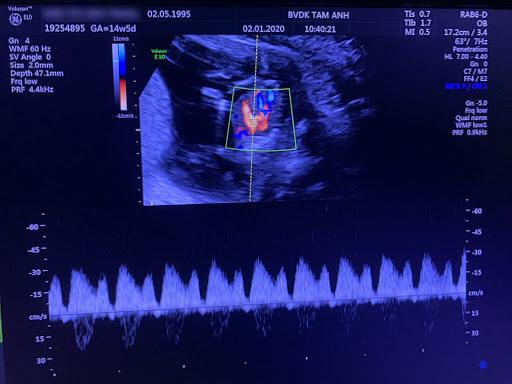

Một ngày tháng 05/2020, thai phụ N.T.L.T. (25 tuổi, ở Thanh Xuân - Hà Nội) nhập viện BVĐK Tâm Anh, Hà Nội khi thai mới 14 tuần 5 ngày, chẩn đoán bị hội chứng truyền máu song thai tình trạng rất nặng, thai chậm tăng trưởng (IUGR) với một thai gần như không còn sự sống, mất sóng Doppler động mạch rốn, Doppler ống tĩnh mạch Arantius ghi nhận mất sóng a. Điều này đồng nghĩa với việc một thai sẽ ngừng tim chỉ trong vòng 24 giờ, thai còn lại cũng đối diện với nguy cơ tử vong.

Để thực hiện được phẫu thuật này đòi hỏi phải có chuyên gia giàu kinh nghiệm, có kiến thức, kỹ năng; Bệnh viện phải có phương tiện máy móc hiện đại và có phòng mổ vô trùng tuyệt đối. Hội tụ đầy đủ cả 3 yếu tố quan trọng này, BVĐK Tâm Anh đã phẫu thuật thành công hơn 200 ca TMST và tiếp tục thành công với ca mổ cấp cứu cho sản phụ T. Sau hơn 3 giờ phẫu thuật, kết quả ban đầu cho thấy một thai được cứu sống. Chỉ sau vài giờ, siêu âm kiểm tra cho thấy tuần hoàn thai nhi phát triển, nước ối trở về mức độ an toàn.